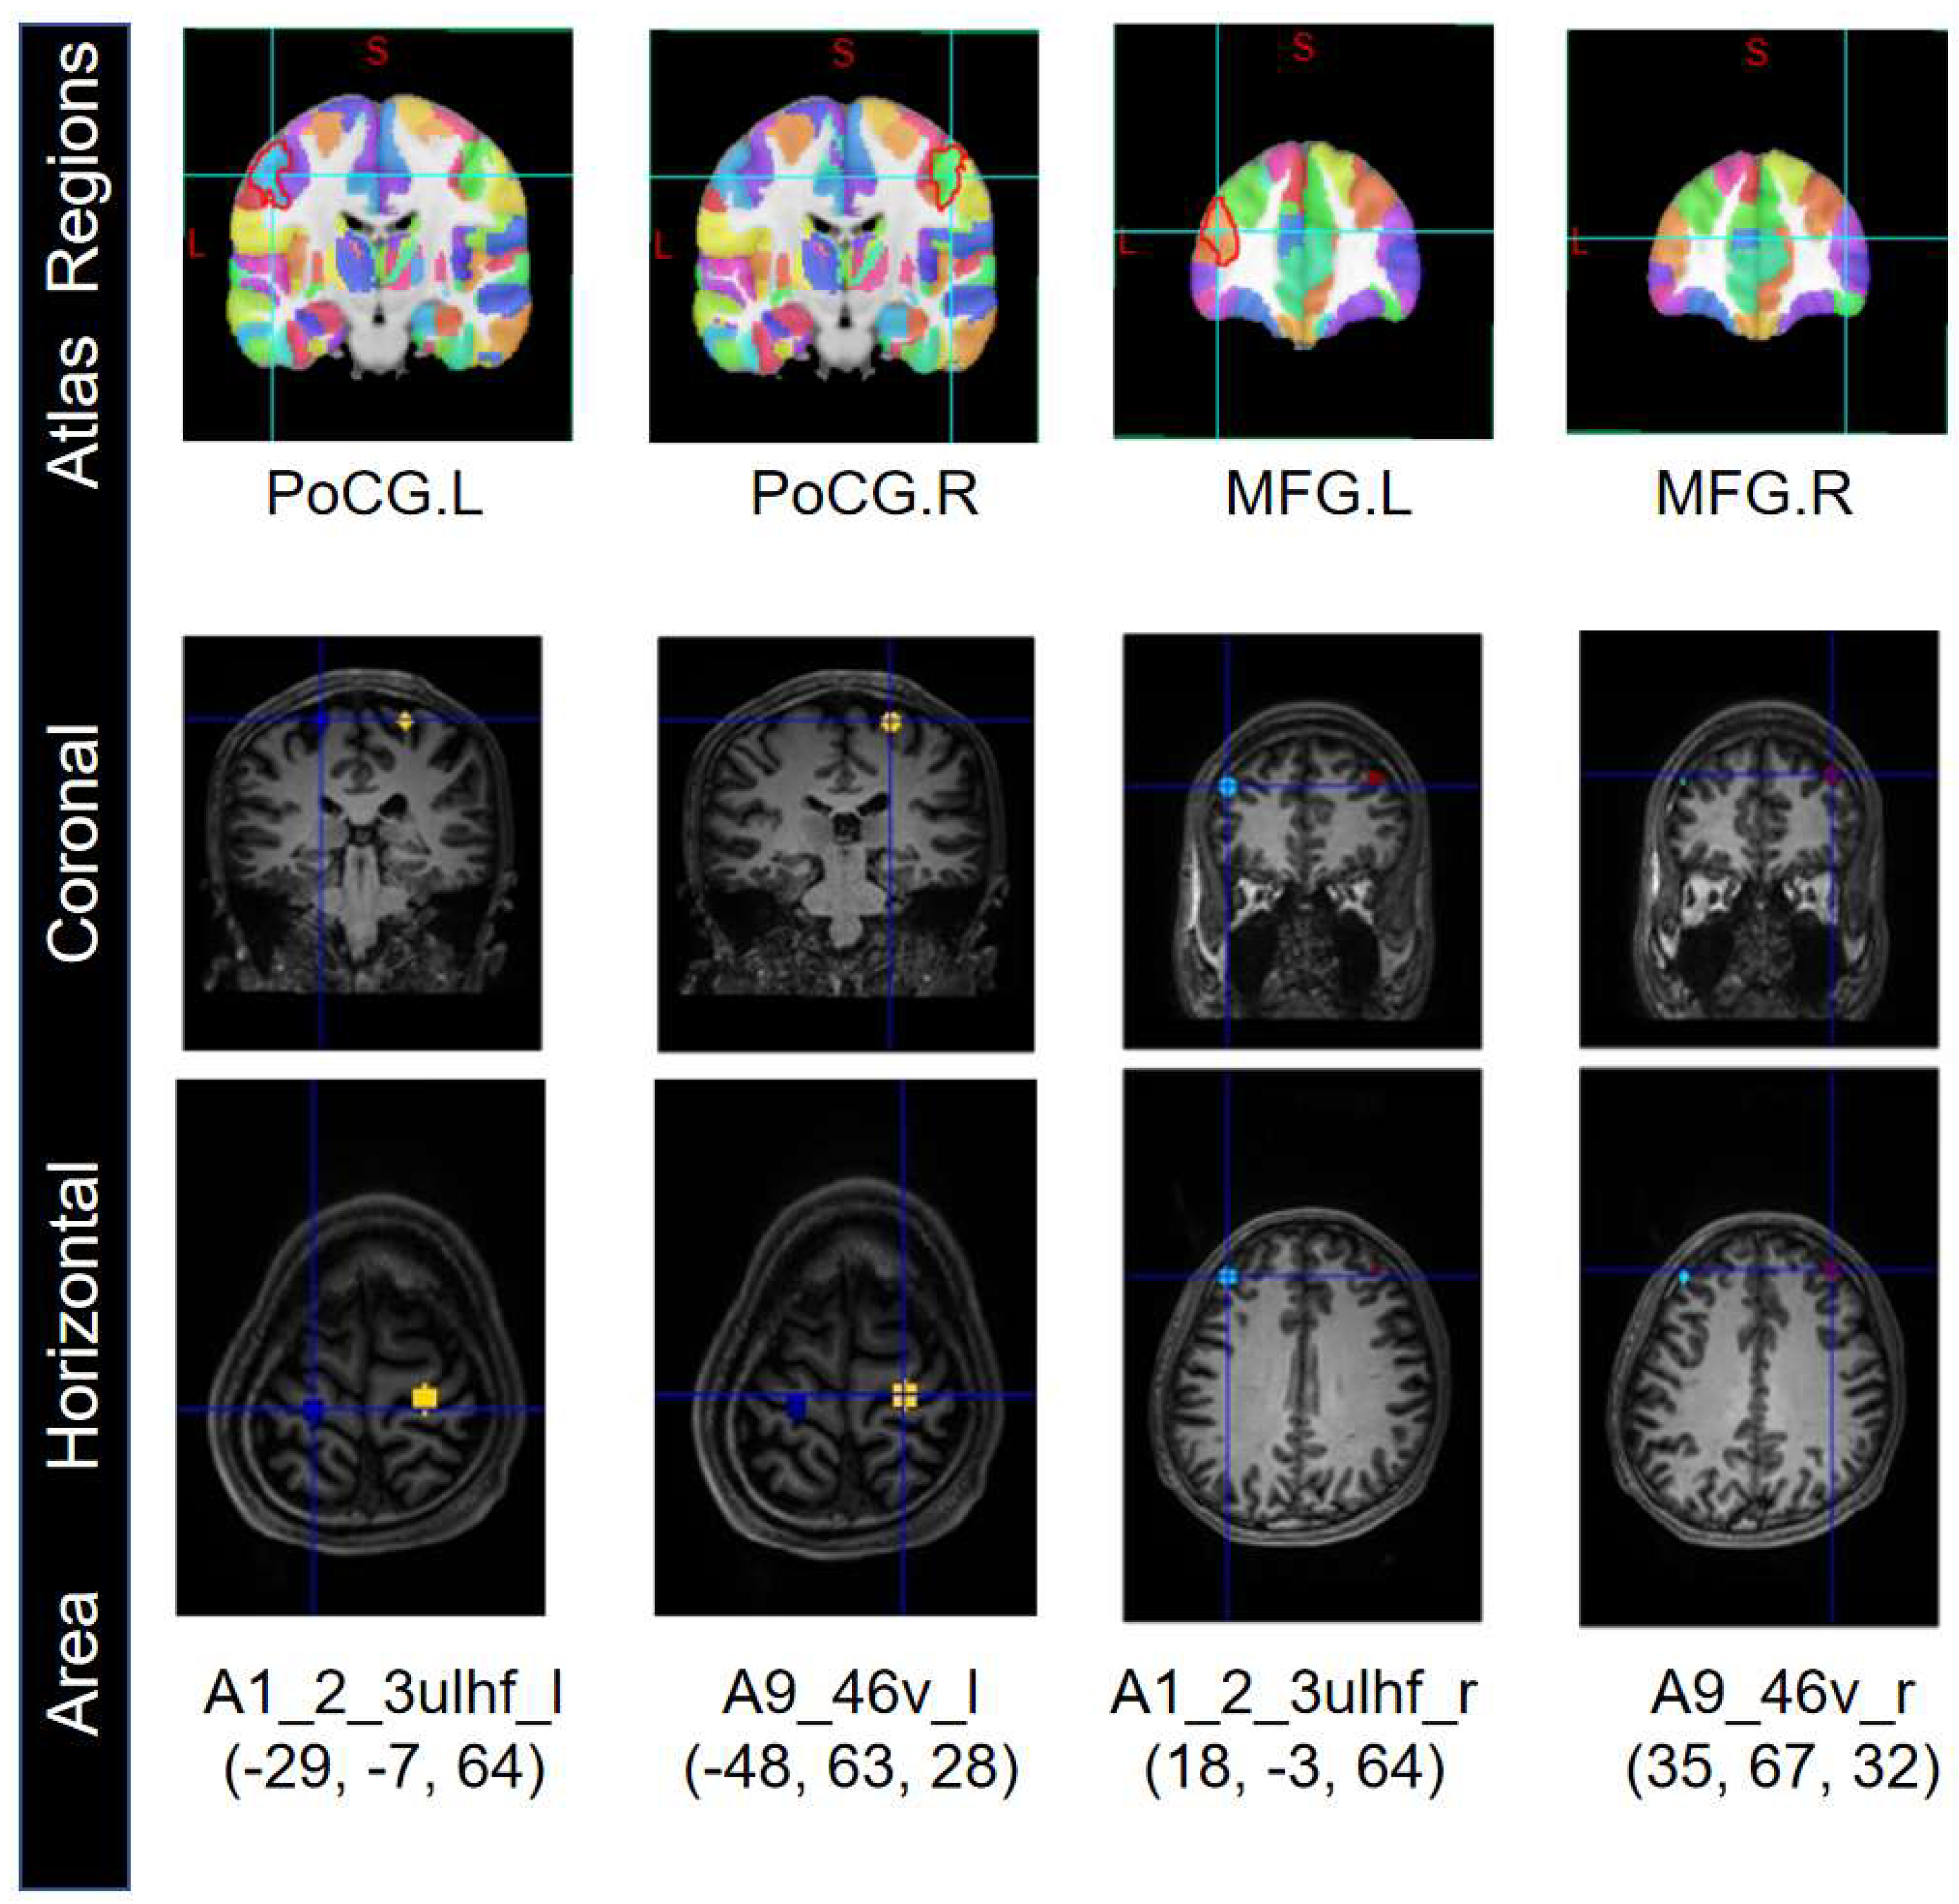

Research has shown that GCM is an effective method for studying functional connectivity based on fMRI data. But this method of fMRI data processing is sensitive to the ROIs, so we selected seed nodes from the ROIs for Granger causality analysis. Based on the brainnetome atlas of 246 brain regions published by the Chinese Academy of Sciences [16], we extracted four seed nodes with the highest correlation after T-test from the ROIs: A1_2_3ulhf_l, A9_46v_l, A1_2_3ulhf_r, and A9_46v_r (Figure 4).

Then, we determined the coordinates of these seed nodes' ROIs. The ROI radius for A9_46v_l and A9_46v_r was set to 5mm, while the ROI radius for A1_2_3ulhf_l and A1_2_3ulhf_r was set to 10mm. Taking Sub1 as an example, the Talairach coordinates (x, y, z in mm) for A1_2_3ulhf_l, A9_46v_l, A1_2_3ulhf_r, and A9_46v_r are (-29, -7, 64), (-48, 63, 28), (18, -3, 64), and (35, 67, 32) respectively.

The brain regions to which these nodes belong, in the Brainnetome atlas, are associated with motor execution, finger movement, cognition, and memory functions. Then, based on temporal invariance, the extracted mean BOLD sequences from the seed nodes were subjected to DWGC analysis.

Figure 4. The selected four seed nodes correspond to the Brainnetome Atlas(Sub 1).